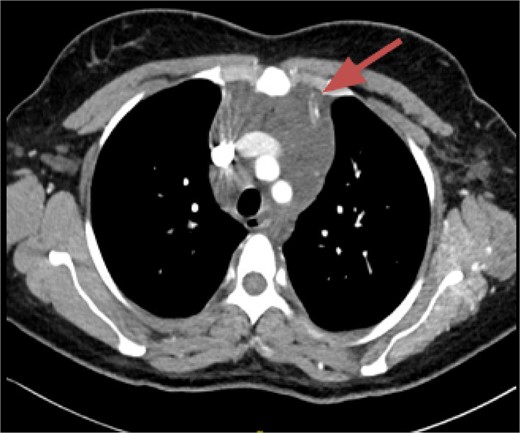

CT imaging, an anterior mediastinal mass was evident (Fig. 2), associated with the presence of thickening of interlobular septa in both lungs (Fig. 3). Surgery is carried out with diagnostic intent with suspicion of lymphoma vs DLP. A mass with cystic characteristics was found, thickening of interlobular septa and lymphatic channels that extended from the lung parenchyma to the mediastinum through the peribronchovascular space, dark serohematic pleural effusion without pleural lesions (Fig. 4).